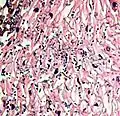

- A severe case of candidiasis